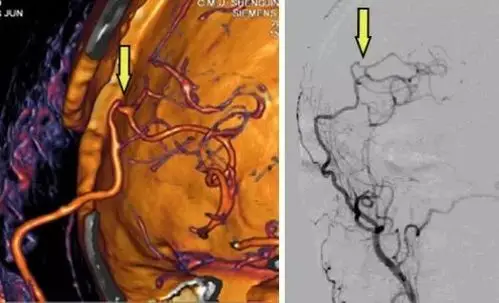

脑血管搭桥重建崭新人生盛京医院喻博教授在烟雾病治疗中的进展